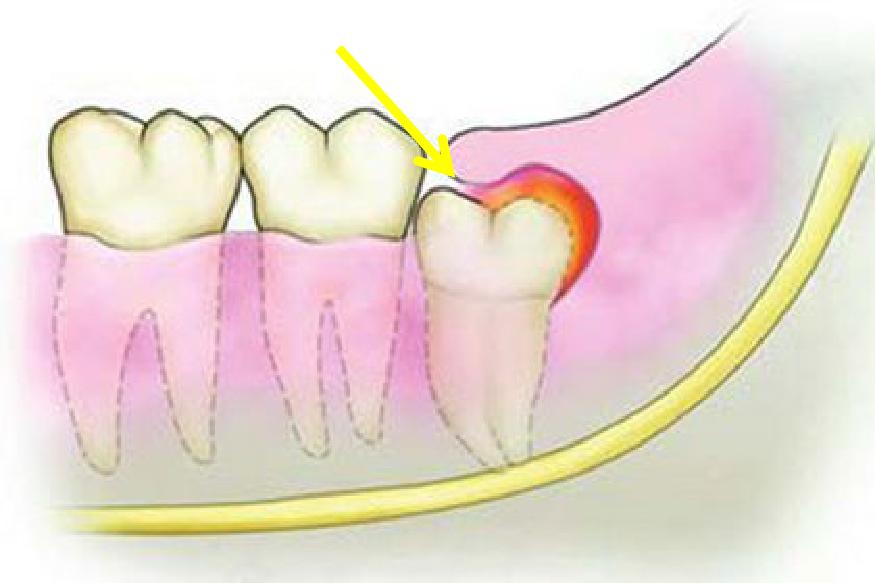

萌出之初,牙冠和牙肉之间形成空隙。上颌因为智齿靠近软腭,刷牙易引起恶心,下颌智齿靠下颌骨的前方,空间有限,牙刷刷头较难深入,清洁不到位,食物残留,细菌聚集,引发感染,称智齿管周炎。

智齿冠周炎常以急性炎症的形式出现。

一般无明显全身反应,可表现为牙冠周围肿胀不适,当进食咀嚼、吞咽、开*活口**动时疼痛加重。

局部可出现放射性痛,炎症侵及周围肌肉出现不同程度的张口受限,甚至“牙关紧闭”,伴有面部的局部肿胀。由于疼痛及张口受限,口腔清洁不足,出现口臭、舌苔变厚、患牙龈袋内挤压有咸味分泌物溢出。